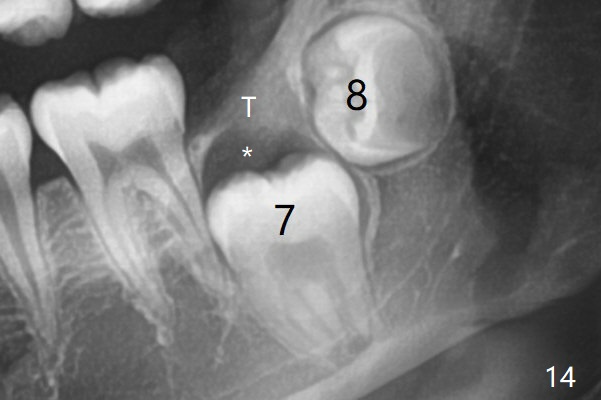

Posterior panoramic X-ray taken immediately pre banding shows impaction of LL7,  blocked by LL8 (Fig.14).   There appear to be a cyst and a tunnel coronal to LL7 (Fig.14 *, T).   CT is mandatory.

The tooth bud of LL8 appears to be close to that of LL7 at the age of 7.5 years (Fig.5).病人7岁时左下智齿牙胚好像已经接近7(图五与右侧比较)。现在左下七冠方仿佛有牙囊(图十四*)和隧道(T)。拔除智齿时,七牙合面骨质应该去除。术前将拍摄CT。